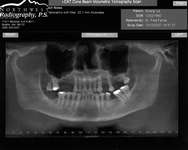

Figure 1A through Figure 1C Buccal and radiographic views of posterior edentulism with significant sinus pneumatization in the molar region.

Figure 1D Lateral wall osteotomy.

Figure 1E The osteotomy was grafted with particulate bone. Figure 1F The surgical site was covered with a resorbable barrier.

Figure 1G Radiographic confirmation of bone regeneration 8 months after surgery. Figure 1H Radiographic confirmation of implant osteointegration into the new bone 14 months after the initial surgery. Figure 1I. Final implant-supported restoration.